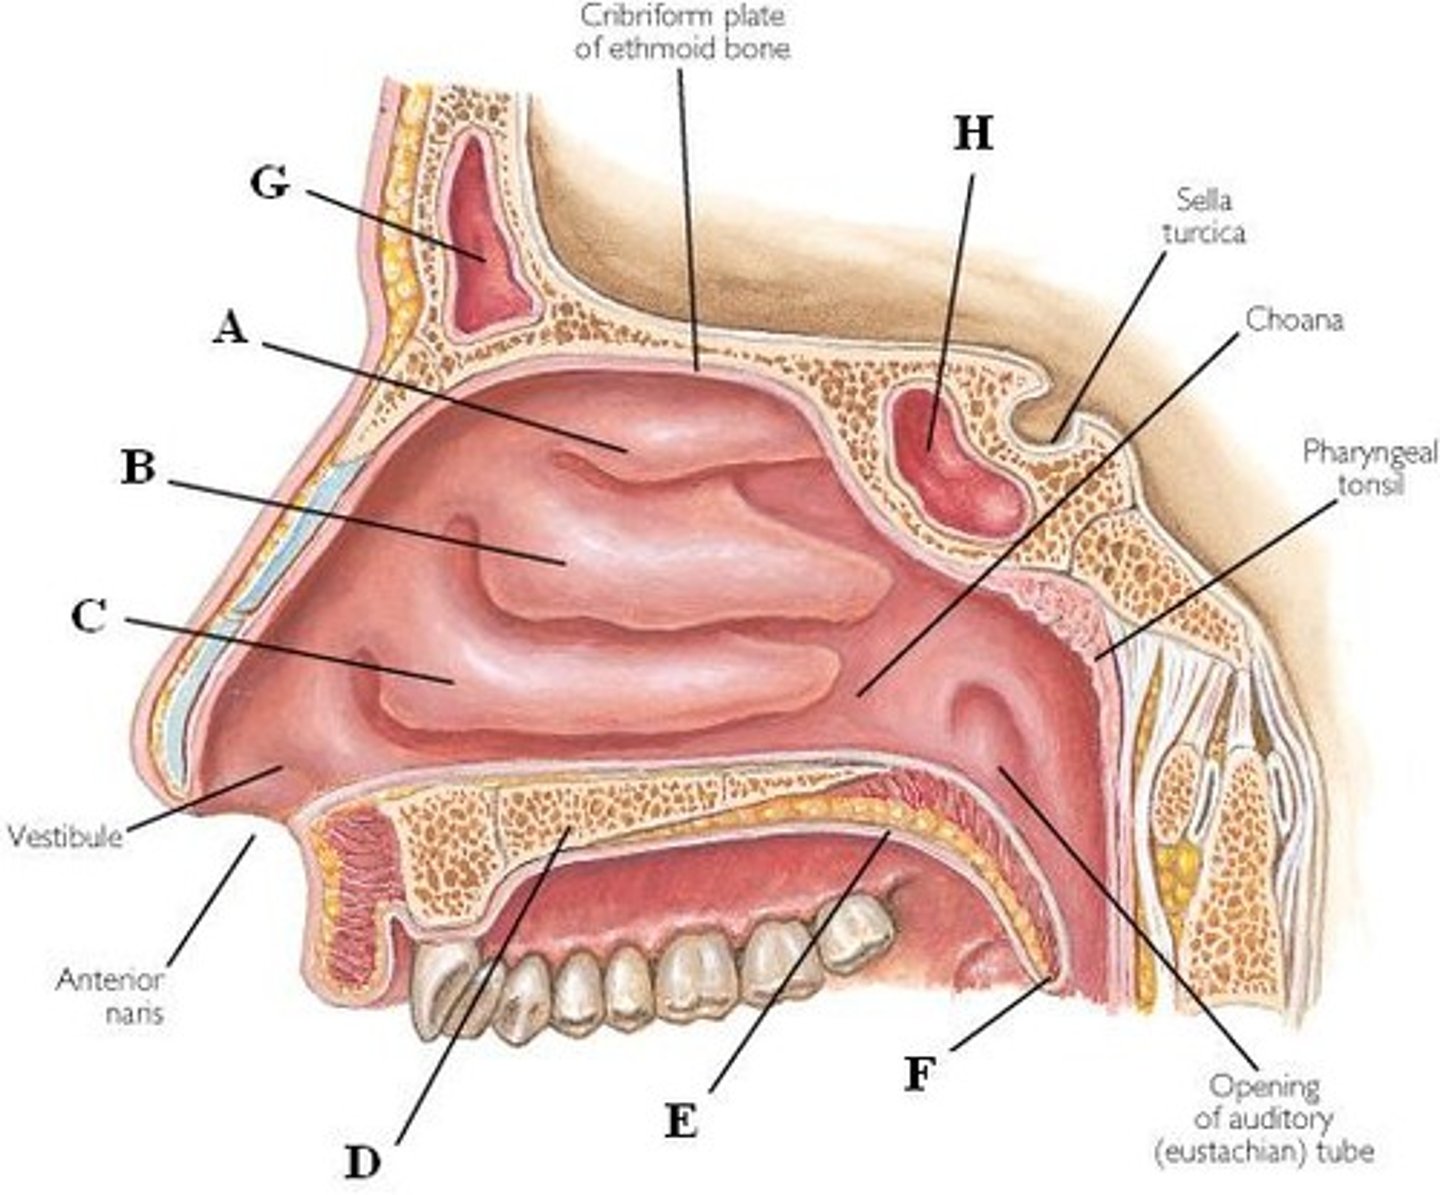

superior nasal conchae

Name A

middle nasal conchae

Name B

inferior nasal conchae

Name C